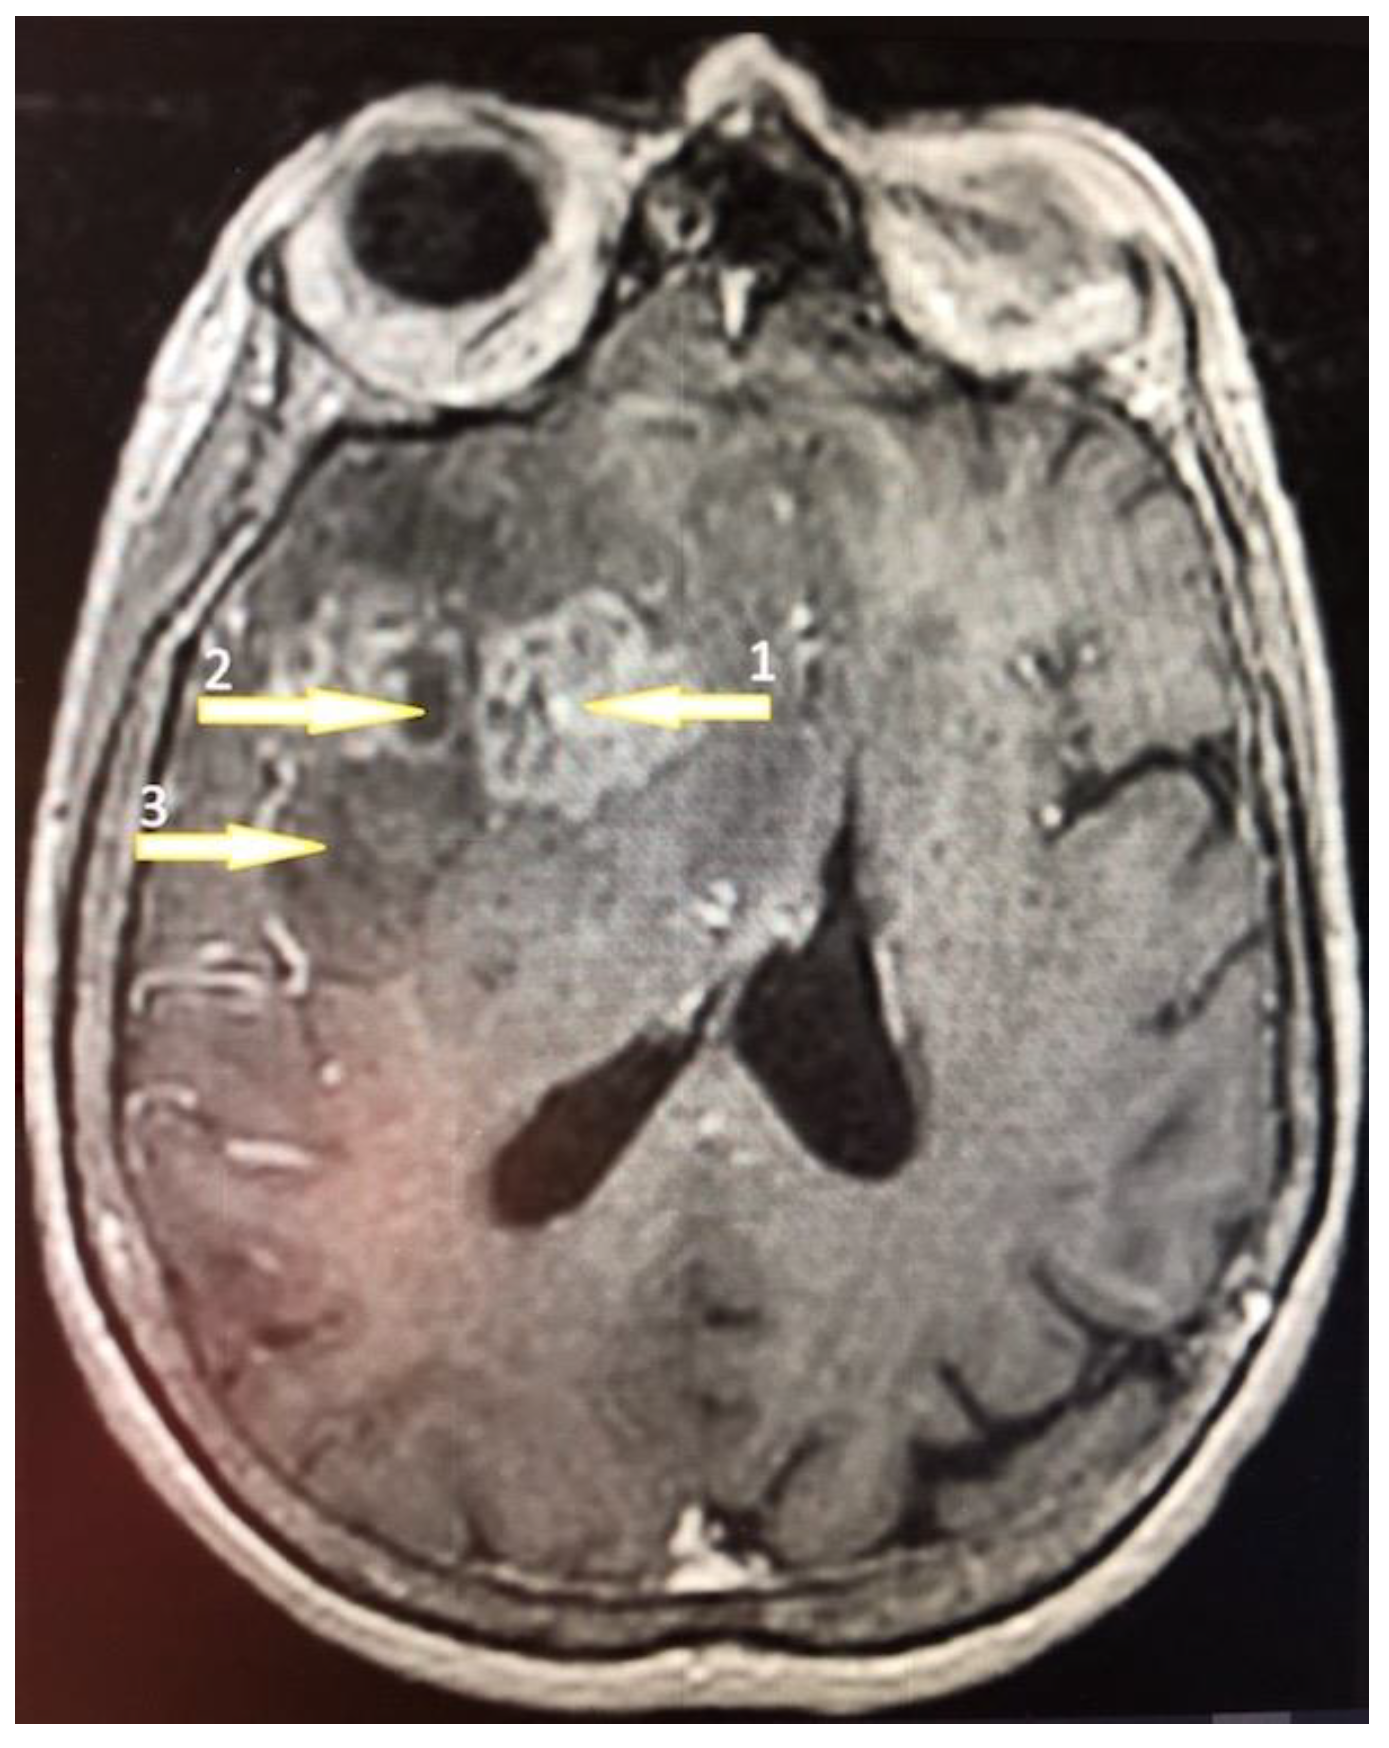

Tumor samples were collected from two regions of the glioblastoma tumor (Figure 1) [48,49]: the non-enhancing tumor core located in the central part of the glioblastoma tumor and the enhancing tumor region, which usually surrounds the tumor core. A sample was also taken from the peritumoral area, which is a commonly used control in glioblastoma research that is compared to the glioblastoma tumor [50].

Figure 1. A 61-year-old high school teacher was admitted to the department of neurosurgery on a day of a seizure episode. She was confused and developed a palmomental reflex on her right side with no other symptoms. Brain nuclear magnetic resonance (NMR) with contrast enhancement revealed a multiform expansive mass in the left frontal lobe with an irregularly shaped growth zone (1) and necrotic core (2) surrounded by the peripheral edematic area (3). The tumor was removed totally by craniotomy and the patient was discharged on the 8th day postoperatively. The pathology revealed a GBM diagnosis and the patient was treated subsequently by an irradation dose of 60 Gy.